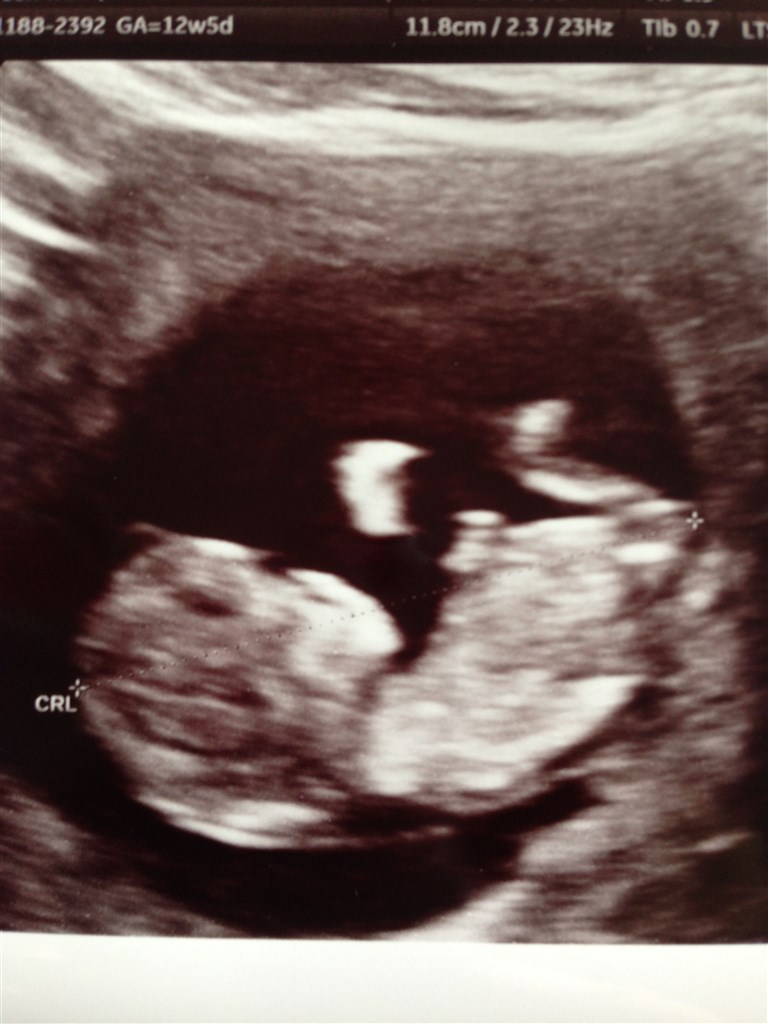

Efter ca. 30 min scanning fik vi afvide alt så rigtig fint ud og den lille stædige baby som ikk ville det samme som scanningsdamen havde fine tal på 1:18916 samt alt det andet den skal ha. Vi er så glade. Vi fik endda lige 2 3D billeder med samt 2 alm.

Vedhæftede fotos (klik for at se i fuld størrelse)